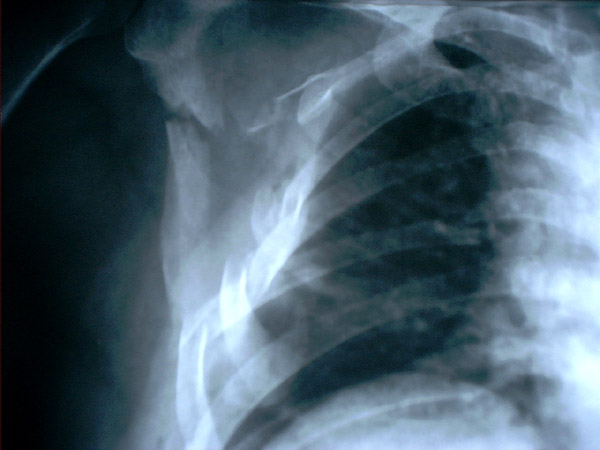

MO Fractura de omóplato y de costillas 2 a 8 derechas. Accidente de tráfico con moto en paciente centenaria. 1

MO Fractura de omóplato y de costillas 2 a 8 derechas. Accidente de tráfico con moto en paciente centenaria.2